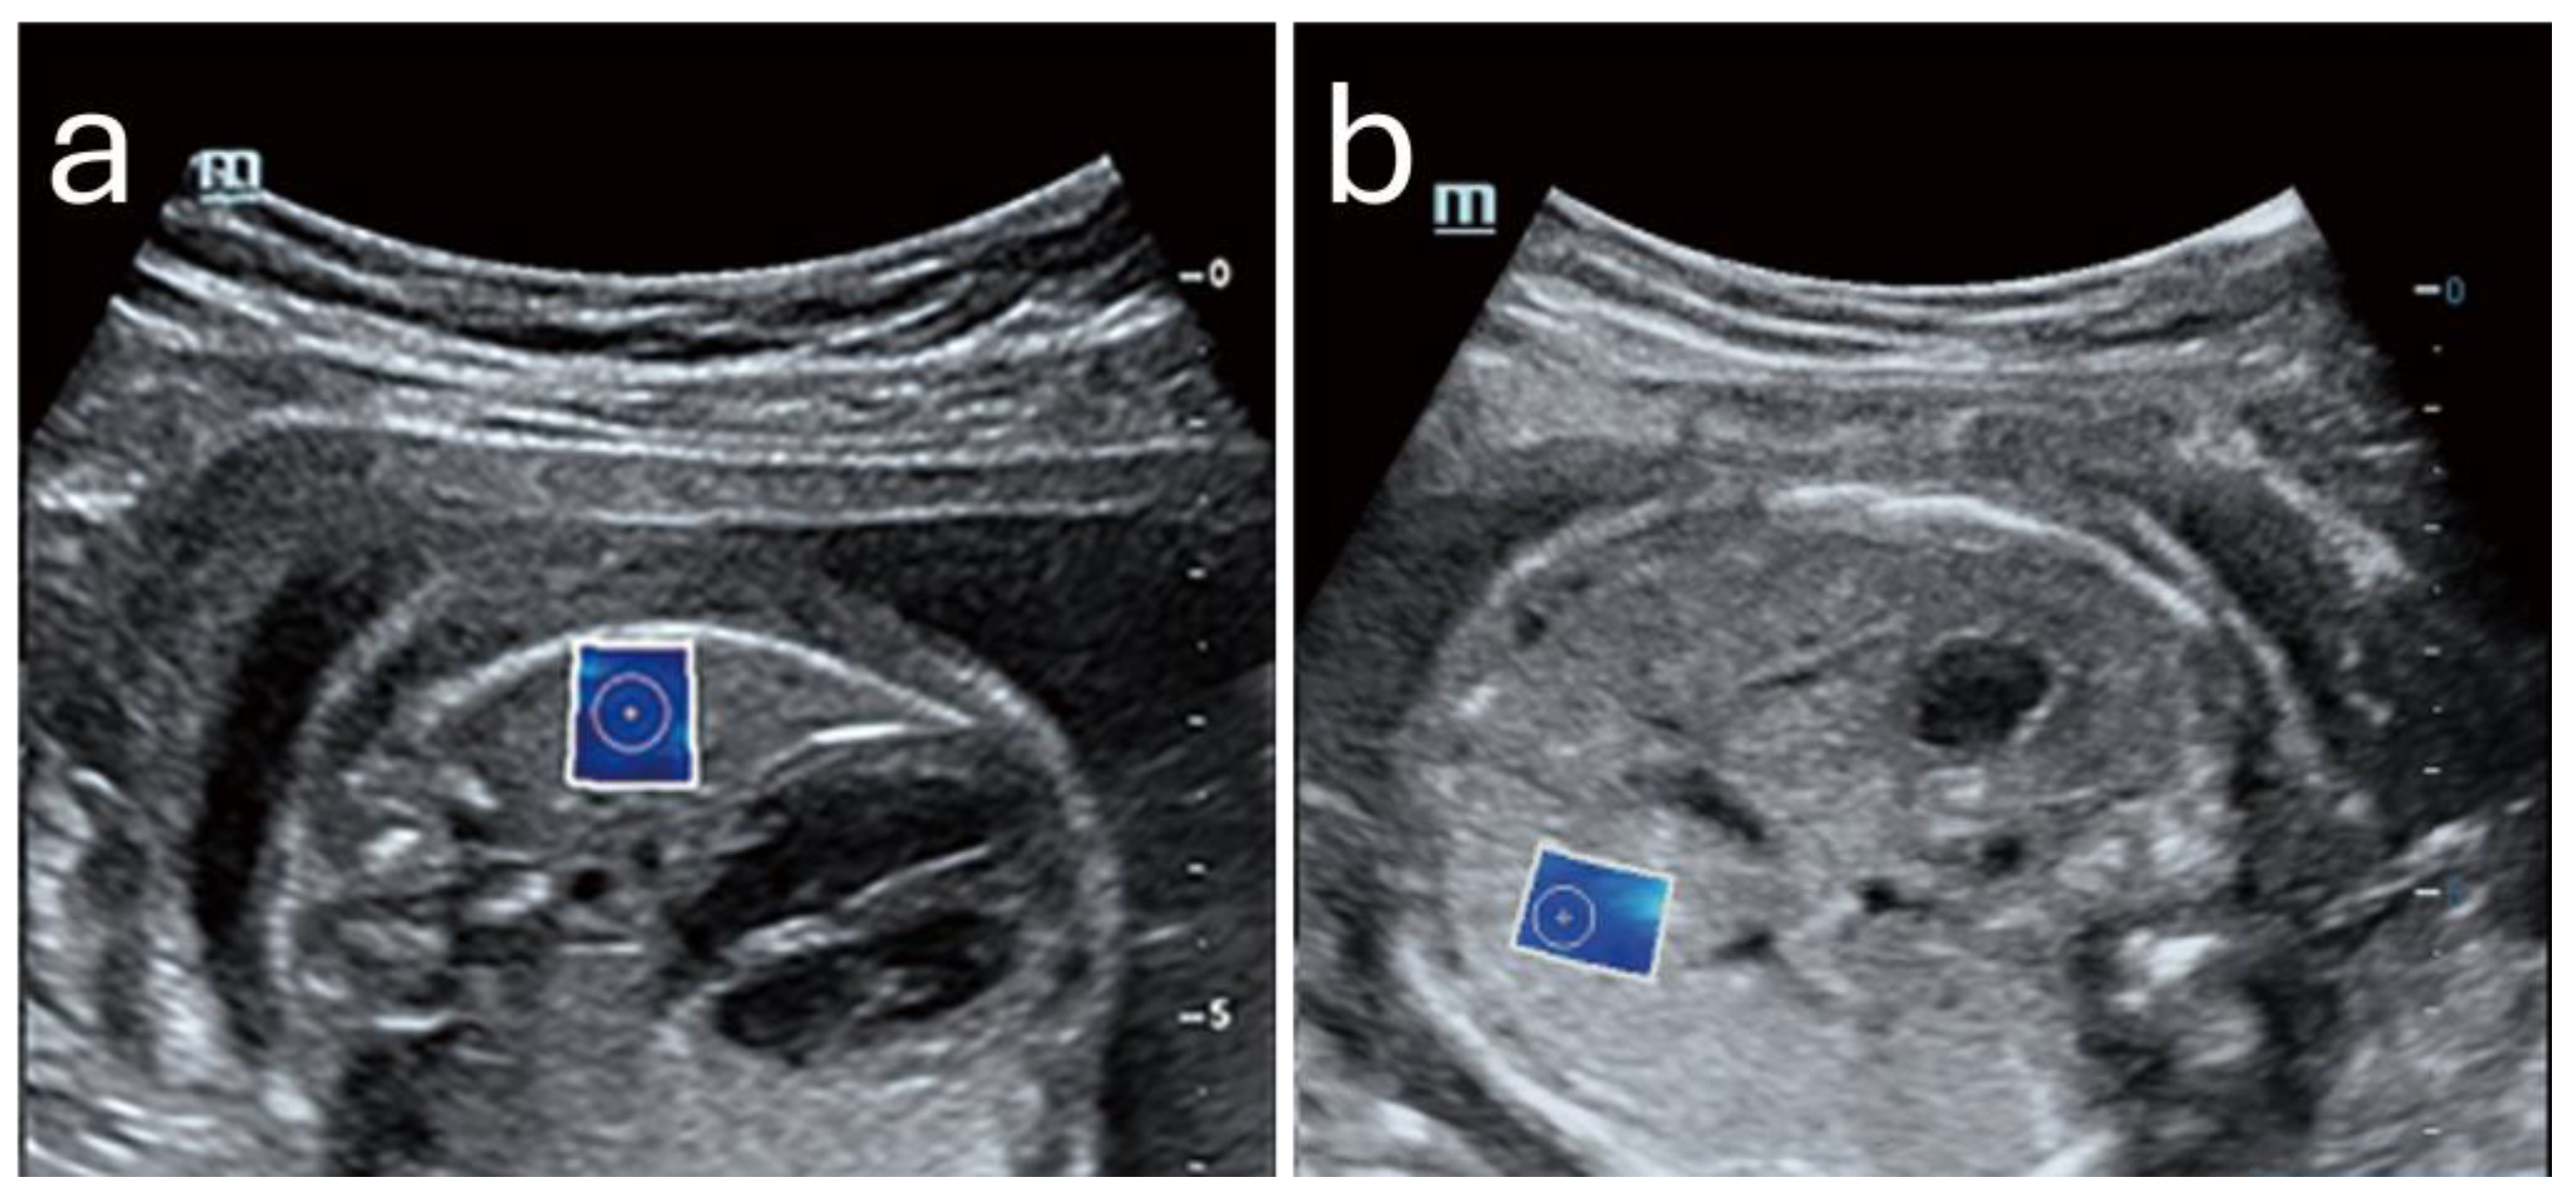

Furthermore, a 2024 study demonstrated that SWE could precisely measure tissue elasticity at specific cervical points, such as the inner and outer cervical os, yielding predictive values higher than cervical length alone. When incorporated into a multifactorial model that included cervical length and pregnancy-related comorbidities, SWE achieved an AUC of 0.892, with a sensitivity of 86.7% and specificity of 79.2%. It also showed that SWE values were lower in PTB (8.76 kPa ± 3.04 kPa) in comparison to full-term pregnancies (14.95 kPa ± 8.21 kPa). All of these positive findings were only valid when the samples where acquired from the anterior or posterior lip of the internal os. An example is shown in Figure 1. This combined approach shows promise for developing a more comprehensive PTB risk model that integrates both elastographic data and clinical factors [15].

Figure 1. (a) Shear wave elastography image from a 26-year-old woman at 35 weeks gestation, showing high stiffness (11.1 kPa) in the anterior internal os; this patient delivered naturally at 38+4 weeks. (b) Shear wave elastography image from a 31-year-old woman at 34 weeks gestation, showing reduced stiffness (4.8 kPa) in the anterior internal os; this patient experienced preterm birth at 35+2 weeks due to premature rupture of membranes. Image adapted from Smith et al. [15] under a Creative Commons Attribution 4.0 International License. Changes were made to resize and adjust the images.